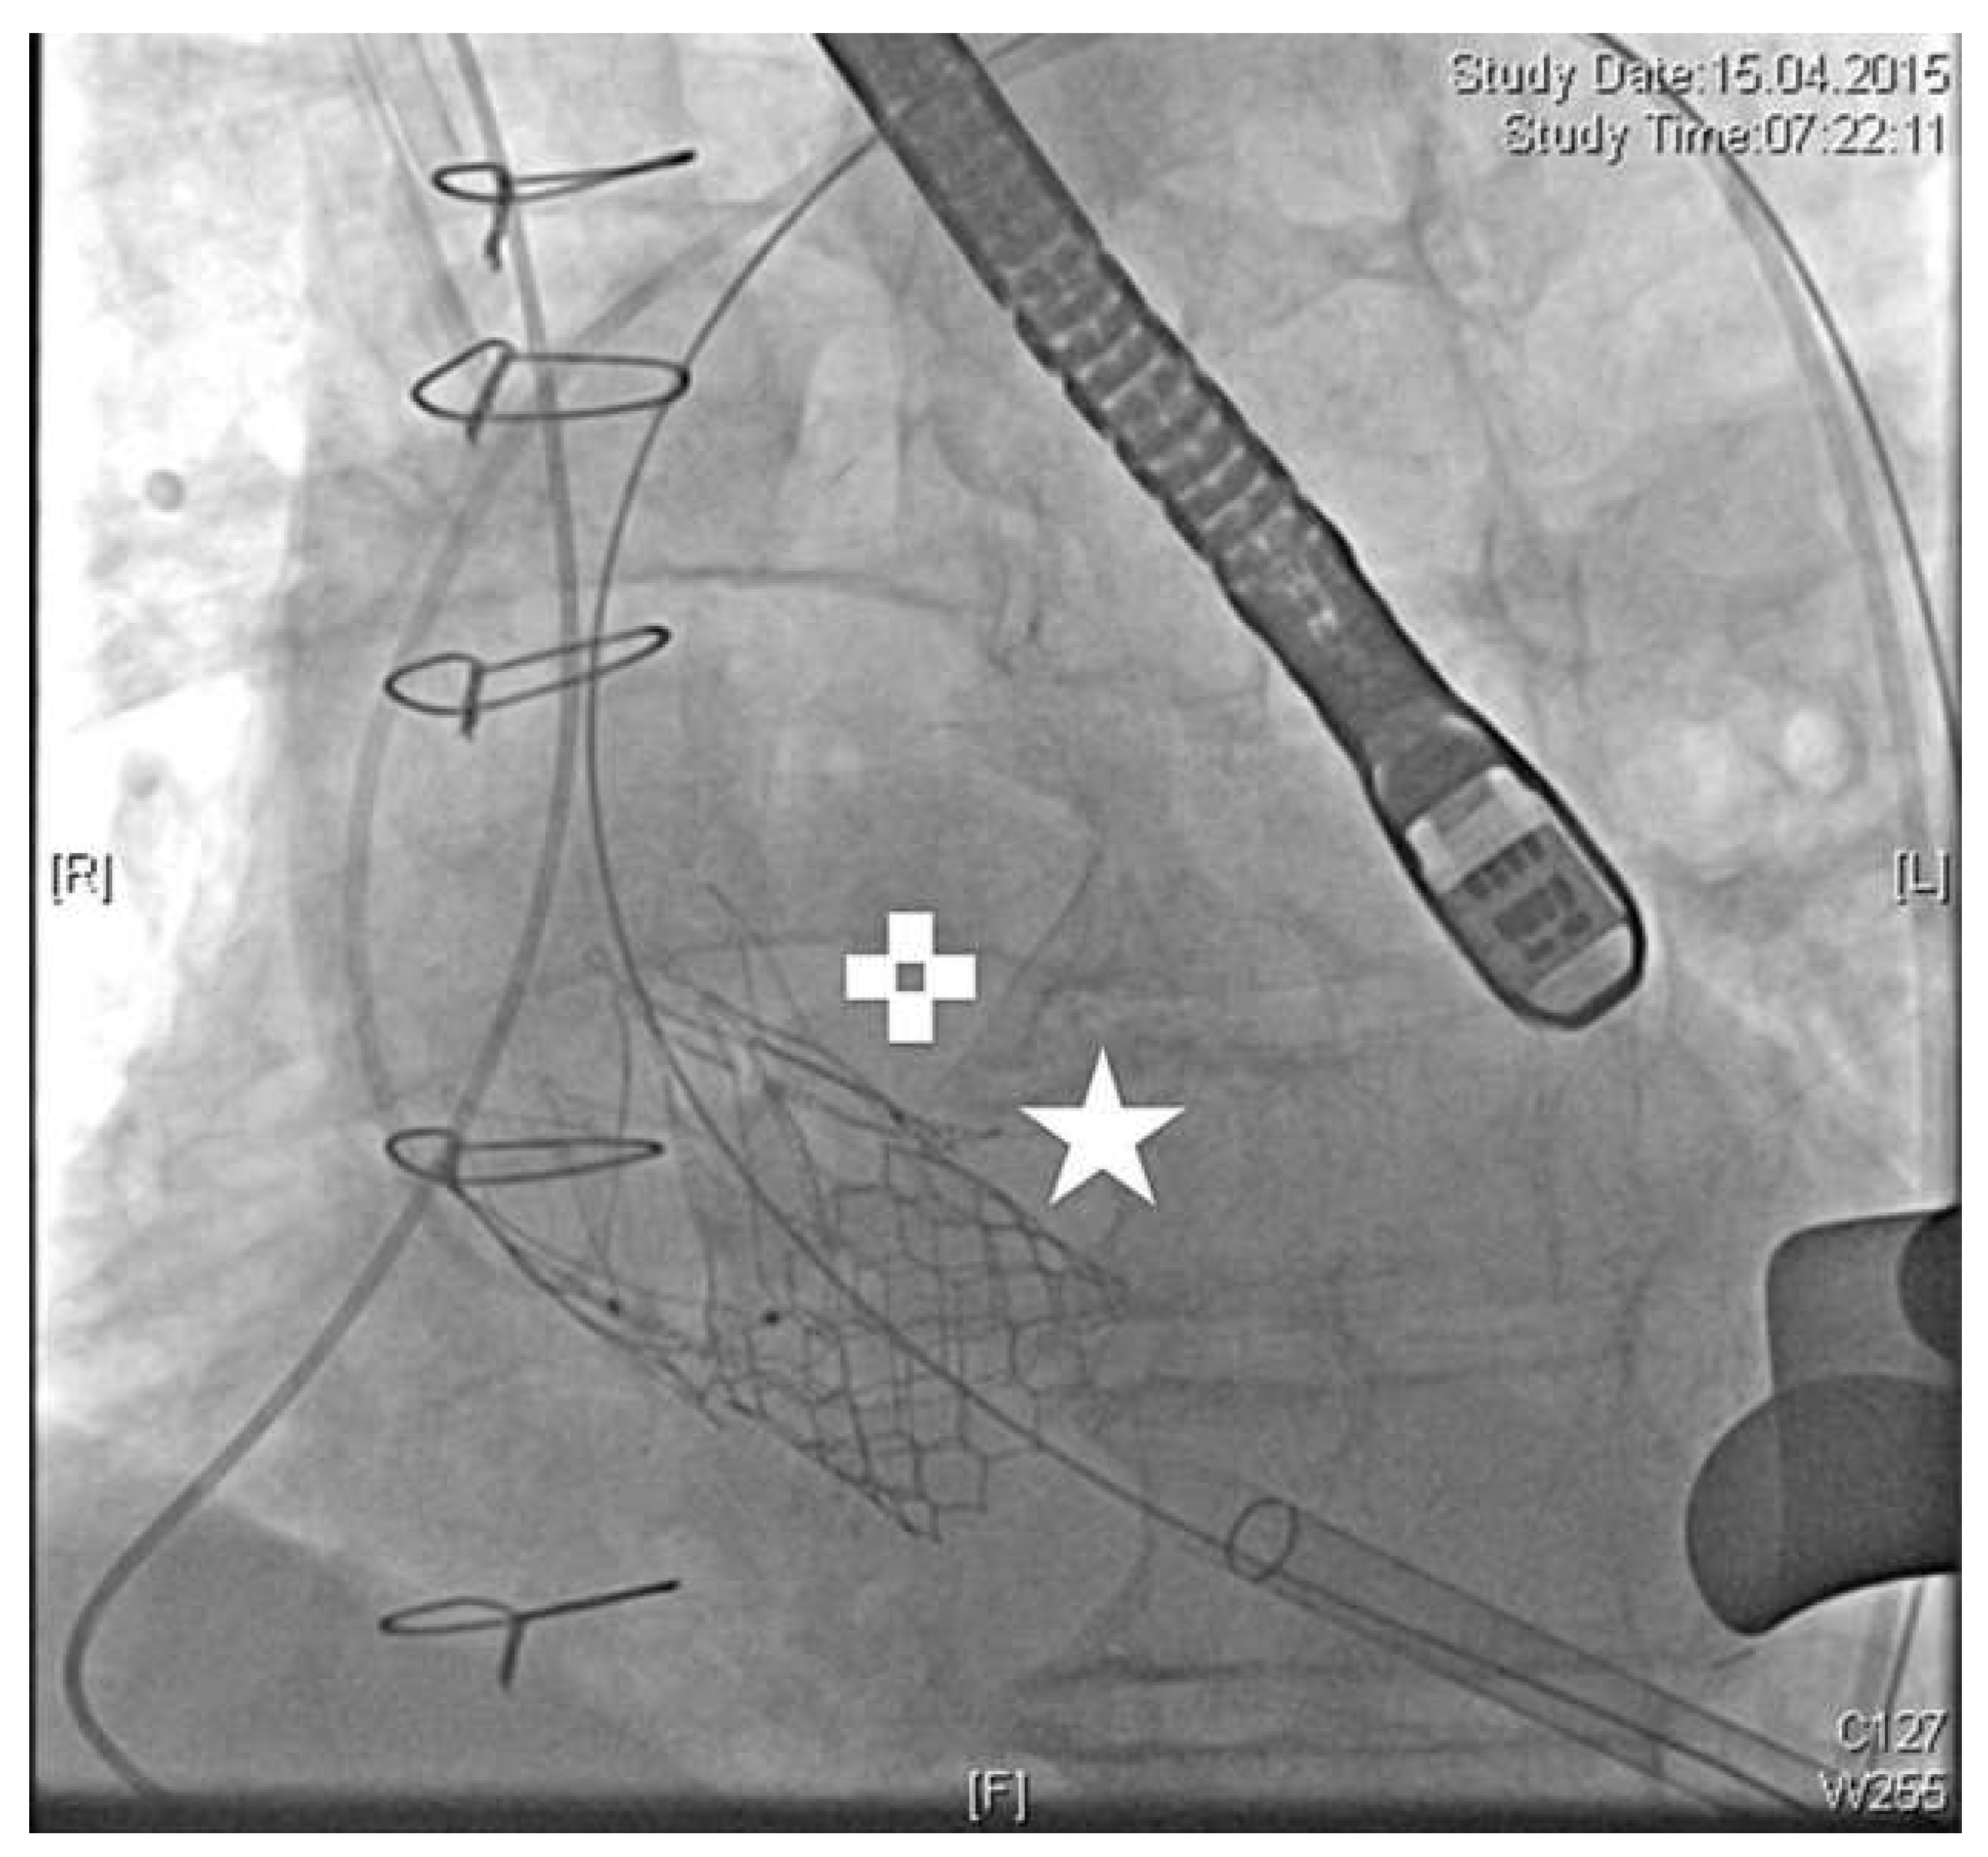

Under general anaesthesia the apex was accessed in the fifth intercostal space. Pericardial adhesions were detached and purse-string sutures applied. Under rapid pacing, straight valvuloplasty was performed and the JenaValveTM subsequently introduced. After release of the positioning feelers they were placed in the sinuses of the native valve. Because of imperfect positioning, the feelers of the JenaValveTM were repositioned. Simultaneously, one of the three eyelets of the crown inadvertently popped out of the catheter tip (Figure 1). Thus the valve became immobile and could no longer be replaced or removed. It had to be finally released at the level of the sinotubular junction. Severe paravalvular leakage could be determined angiographically and echocardiographically. Fortunately the patient was haemodynamically stable and no signs of myocardial ischaemia were detected. Because of the severe atherosclerosis of the native coronaries, as well as the sufficient myocardial perfusion via bypass grafts, conventional reoperation with sternotomy as bailout was rejected and implantation of a second TAVI prosthesis favoured instead. Therefore, a 26-mm Sapien S3 valve (Edwards, Irvine, USA) was chosen and uneventfully implanted transapically. The prosthesis was positioned directly beneath the JenaValveTM resulting in a valve-under-valve situation (Figure 2). Angiography and echocardiography revealed overall minimal paravalvular leakage at the level of the right coronary sinus with a total mean gradient of 8 mm Hg. After 145 minutes of total procedure time, the patient was extubated in the hybrid room with no inotropic support and without any neurological deficit. Maximum troponin T was 0.313 μg/l. After 24 hours of intensive care he was transferred to the normal ward and discharged from hospital on postoperative day 9. Predischarge ECG-triggered CT angiography showed both TAVI prostheses in situ, no signs of perforation and perfused bypass grafts. Predischarge transthoracic echocardiography confirmed the minimal paravalvular leakage and an acceptable gradient of mean 12 mm Hg. One year after discharge the patient was presenting well. His latest echocardiographic follow-up (April 2016) revealed a slightly reduced ejection fraction (50%), mild paravalvular leakage (grade 1) as well as a peak/mean pressure gradient of 16/8 mm Hg.

Figure 1. White arrow shows one of the three eyelets of the crown inadvertently and incorrectly popping out of the catheter tip.